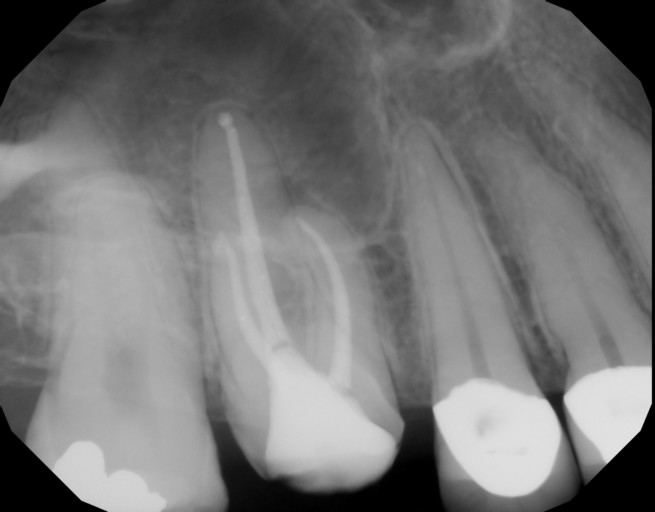

Damaged inferior alveolar nerve during root canal

I had a root canal on a lower molar, not quite a week ago. I had broken the tooth upon chewing two days before, they did xrays and I was told I needed a root canal. I was in the chair for 6 hours, I was told due to the fact that my roots on this tooth curved and care had to be taken to get it all and not break the drill off. I also have very bad pressure hives, so two hours into the procedure my lower jaw,face, started swelling. I didn't think too much about his because of the hives and the assistant was pulling pinching the cheek/mouth out the the way. I have a super tiny mouth and this has alway been a problem with dentist, they used an extra small childs dental block to keep my mouth open. After 6 hours of being in the chair, I told them I had had enough for the day, my face was very swollen, and the dentist hadn't even put the temporary crown on yet but I told him I would be back the next day. After the novicain started wearing off which took hours, I still couldn't feel my lower left lip or my chin. I canceled my appoint for the next day and just thought the numbness was from the pressure hive. The next day I called the dentist and told him that I was still numb and they told me to come in the next day. He told me that it was the alveolar nerve and did a pan scan which I guess they have a "non digital" scanner, which basically told them nothing. He said that I need to go to an oral surgeon to have them assess the nerve. I also have a large lump where the hive was, it was painful but I think its gradually getting smaller, I am concerned about that but more concerned with the nerve. Will this nerve and feel come back? Is this a common occurance? The dentist said he never has heard of this happening except in the case of wisdom teeth extractions. I should also add that the gum between the premolar and first molar is numb as well. Not sure this is the first molar since I had so many pulled when I was younger and getting braces on. I think this must be my second molar in reality. I am very scared that this is going to be permanent. I have terrible dental phobia as it is but this is putting me over the edge. I would appreciate any help you can give me. Is there anything that I could do to help the nerve, i.e. massage, vitamins, etc.? Thank you so much for your time! Susan